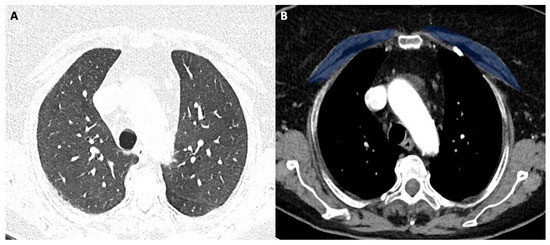

Figure 1 shows the modality of PMD and PMA evaluation. Figure 2 and Figure 3 show the examples of two patients enrolled in the study.

Figure 1A shows the CT-slice selection and the pectoral analysis. Figure 1B shows the pectoral muscle area (34.2 cm2) and pectoral muscle density (30.2 HU) analysis of the pectoralis major (green-blue area) and minor (yellow area). Figure 1C shows the corresponding lung disease (pneumonia severity index score: 7). The patient had a short ICU stay, and he had successful extubation.

Figure 1. (AC) 56-year-old male with COVID-19.